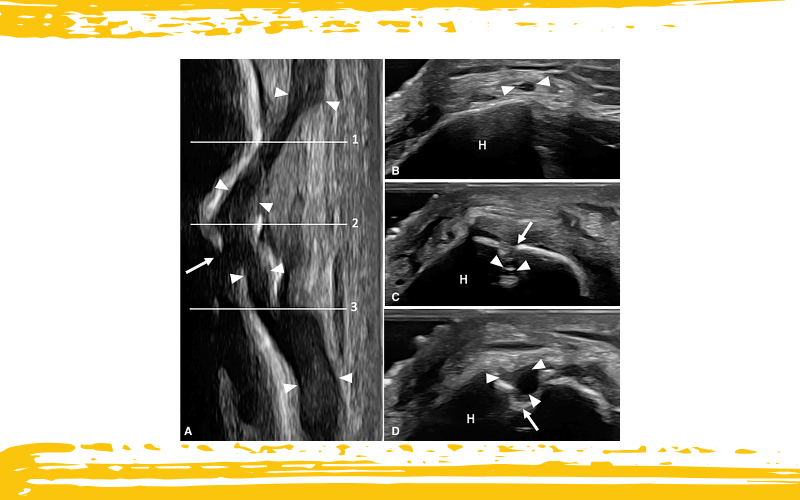

Varón de 34 años que presenta dolor y parestesias en la cara posterolateral del antebrazo y sobre el epicóndilo lateral, iniciados 2 semanas después de una fractura supracondílea de húmero.

La exploración ecográfica reveló atrapamiento del nervio cutáneo posterior del antebrazo (PCNF) a nivel del foco de la fractura en proceso de consolidación.

En la imagen A, la vista ecográfica longitudinal (puntas de flecha blancas) muestra cómo el nervio se desvía de su trayecto habitual, quedando incluido dentro de la línea de fractura (flecha blanca).

Las imágenes B, C y D presentan tres cortes ecográficos axiales secuenciales del PCNF (puntas de flecha), obtenidos en las líneas 1, 2 y 3 señaladas en la imagen A, respectivamente. Estas imágenes ilustran el trayecto del nervio a través de la línea de fractura (flecha blanca).

Se observa una pérdida completa de la ecotextura fascicular, acompañada de aumento del calibre del nervio tanto proximal como distal al foco de la fractura.

H: húmero.